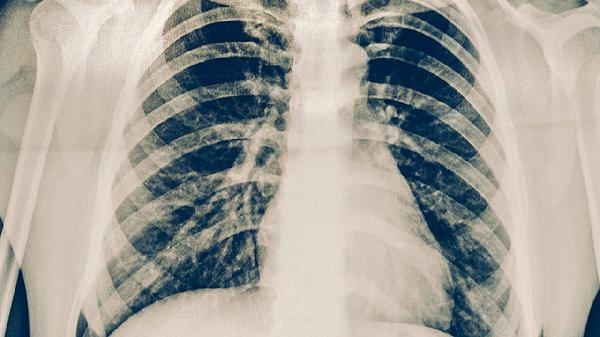

术后短期内出现的磨玻璃结节常见于局部组织修复过程中的炎性反应,尤其是胸腔镜手术后的胸膜粘连或肺泡出血吸收期。这类结节通常边缘模糊、密度均匀,随访中可能逐渐缩小或消失。术后复查的低剂量CT若显示结节形态规则、无血管集束征或空泡征等恶性特征,更倾向良性病变可能。对于存在高危因素如长期吸烟史或家族肿瘤史的患者,需警惕多原发肺癌可能,此时结节多表现为持续存在或缓慢增长。

当磨玻璃结节呈现分叶状、毛刺征等典型恶性征象,或随访中体积增大、实性成分增加时,需考虑肿瘤复发或第二原发癌可能。微浸润性腺癌本身复发概率较低,但若初次手术切除不彻底,残留的非典型腺瘤样增生可能进展为浸润灶。病理亚型如贴壁型为主的肿瘤更易出现多灶性生长,需通过PET-CT或穿刺活检明确性质。